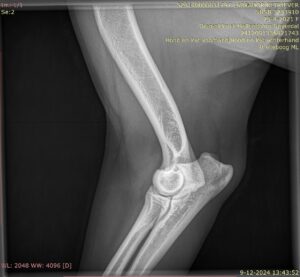

ED (elleboogdysplasie)

Elleboogdysplasie (ED) is een ontwikkelingsstoornis van met name het kraakbeen in de gewrichten. Het kan erfelijk zijn, maar omgevingsfactoren dragen vaak ook bij aan het ontstaan van deze aandoening. Sommige honden kunnen op jonge leeftijd al ernstige problemen ondervinden door ED. Bij andere honden leiden ernstige misvormingen in het gewricht pas op latere leeftijd tot kreupelheid. Om echt te kunnen zien of je hond ED heeft, zijn (digitale) röntgenfoto’s van zijn gewrichten nodig. Het ED-onderzoek richt zich op vier verschillende aandoeningen van het ellebooggewricht. Al deze aandoeningen kunnen leiden tot misvormingen in het gewricht en kreupelheid. Het aantal te maken röntgenfoto’s verschilt per ras. Internationaal komen beoordelaars samen om te zorgen dat alle landen op gelijke manier de ellebogen beoordelen.

Vormen van ED zijn:

- los processus anconeus (LPA) / – los processus coronoïdeus (LPC):

hierbij ligt een stukje bot van de ellepijp los in het gewricht - osteochondrosis dissecans van de mediale humeruscondyl (OCD):

afwijking in het gewrichtskraakbeen van de bovenarm - incongruentie van het gewrichtsvlak van radius en ulna met de humerus:

de drie botten in het ellebooggewricht (spaakbeen, ellepijp en bovenarm) sluiten niet goed op elkaar aan in het gewricht.

Deze vormen kunnen apart of samen voorkomen en elkaar beïnvloeden.

Symptomen zijn pijn en kreupelheid aan één of beide voorpoten. Deze treden al op vanaf een leeftijd van rond 6 maanden. Later ontstaat ook artrose (gewrichtsslijtage).

Er zijn verschillende FCI-einduitslagen mogelijk:

- ED-vrij betekent dat er geen afwijkingen zijn gevonden

- ED 1 (graad 1): Er is sprake van artrose in het gewricht.

- ED 2 (graad 2): Er is verdenking of constatering van een matige vorm van elleboogdysplasie.

- ED 3 (graad 3): Er is verdenking of constatering van een ernstige vorm van elleboogdysplasie.